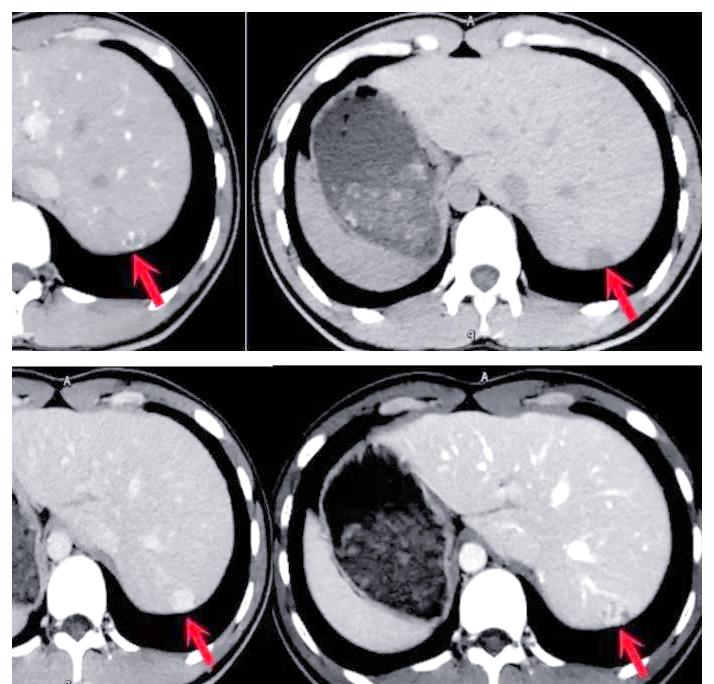

增强CT检查是一种在常规CT扫描基础上,通过静脉注射造影剂来增强图像对比度的检查方法这种检查可以帮助医生更清晰地看到体内的血管器官和病变组织的细节,从而更准确地判断病变的性质和范围当医生建议在手术前进行增强CT检查时,主要是为了获取更详细的影像学信息这些信息有助于医生在手术中更好地。

超强CT,这个名字听起来确实让人感觉新奇,但实际上,它可能就是我们常听说的增强CT增强CT是在普通CT检查的基础上,通过静脉注射一种增强剂,通常是碘剂,然后再进行扫描的一种检查方式这种检查方式能够使得病变区域更加清晰地显示出来,有助于发现那些隐蔽的病变此外,它还能帮助医生了解病变与周围。